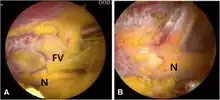

Surgery involves a nerve decompression with or without muscle resection.[5] The surgery can be performed with external incisions (open surgery) or endoscopically. Endoscopy allows for complete sciatic nerve visualization and access for decompression in the extrapelvic gluteal space.[1] The goal of surgery is to restore normal nerve kinematics and nerve conduction. During surgery this is measured by nerve conduction studies and electromyography, as well as observing the sciatic nerve mobility while the patients hips are moved.[1][2] This testing can be done before and after the decompression to verify improvement before concluding the surgery.

The outcomes measures include modified hip harris score (mHHS), VAS score (numerical pain scores), and Bensen outcomes questionnaire.[2] At a 2 year follow up, 80% of patients demonstrated good-to-excellent Benson ratings postoperatively.[2] In one study assessing 122 patients, for pain assessments, 90% improved, 8% had no change, and 2% were worse. For strength assessments, it's 86% improved, 9% saw no change, and 5% were worse. If patients had numbness, then 59% saw improvement and 41% did not see improvement.[7] VAS score changes are consistently positive, with an average of 6.7 preoperative (moderate-severe pain) to 2.1 postoperative (mild pain).[7][30] The endoscopic approach has low complication rate (0% major and 1% minor). Open surgery has higher complication rate (1% major and 8% minor).[7] Major complications are potentially life-threatening and require immediate as well as intensive medical interventions, while minor complications are not life-threatening and can be managed with less aggressive treatment.